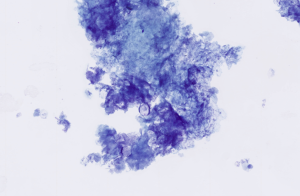

Mesenchymal tumours exfoliate poorly and often produce low-cellularity preparations. When present, cells often appear spindle-shaped, stellate, or elongate, with wispy cytoplasm and oval to elongated nuclei. They frequently lie within or adjacent to pale extracellular matrix, supporting a mesenchymal origin (Figure 16).

Figure 16 – Cytological features of a well‑differentiated sarcoma. The smear shows a population of spindle‑shaped mesenchymal cells arranged individually and in loose aggregates, with moderate pale cytoplasm and elongate to oval nuclei exhibiting mild anisokaryosis. Scattered extracellular matrix (collagen) may be present (red arrows). Modified Wright’s stain, ×40 objective

While cytology can strongly suggest a spindle cell tumour, differentiating benign from malignant is often unreliable, and histopathology is usually required for definitive classification.